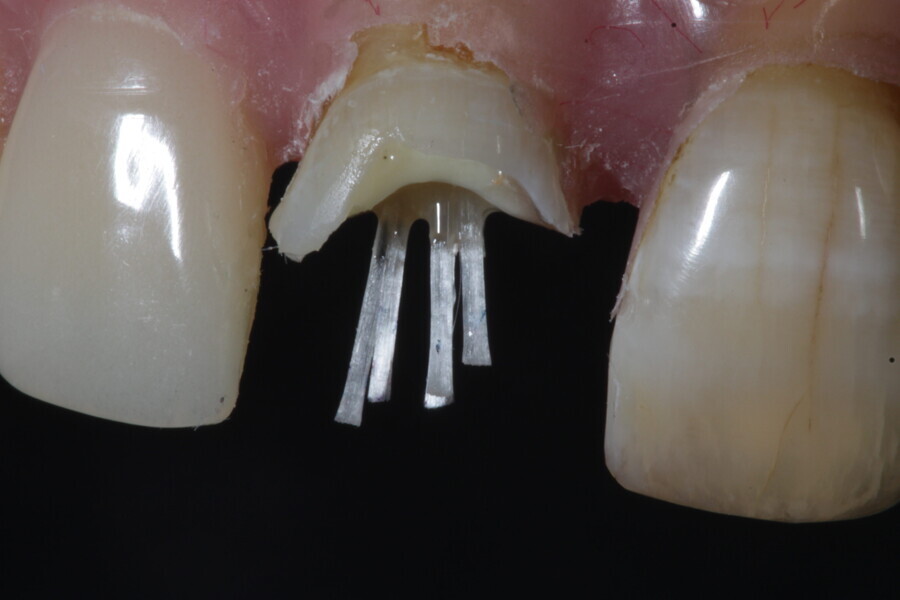

1. functional and aesthetic reconstruction of a maxillary anterior tooth using fibre-reinforced flexible micro-posts after endodontic treatment (Figs. 3–20);

Example 1—showing functional and aesthetic reconstruction of a maxillary anterior tooth using fibre-reinforced flexible micro-posts after endodontic treatment.